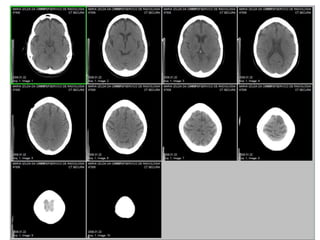

SCOUT/SCANOGRAMA

18

• Radiografia digital realizada em PERFIL para

programação dos cortes.

• Os cortes devem seguir o protocolo de cada

unidade radiológica, mas são geralmente muito

parecidos.

• Uma proposta de protocolo pode ser:

2mmx3mm em fossa posterior e

10mmx10mm em supra tentorial.

CORTES FOSSA POSTERIOR

81

SUPRA TENTORIAL

82

IMAGENS ÓSSEAS